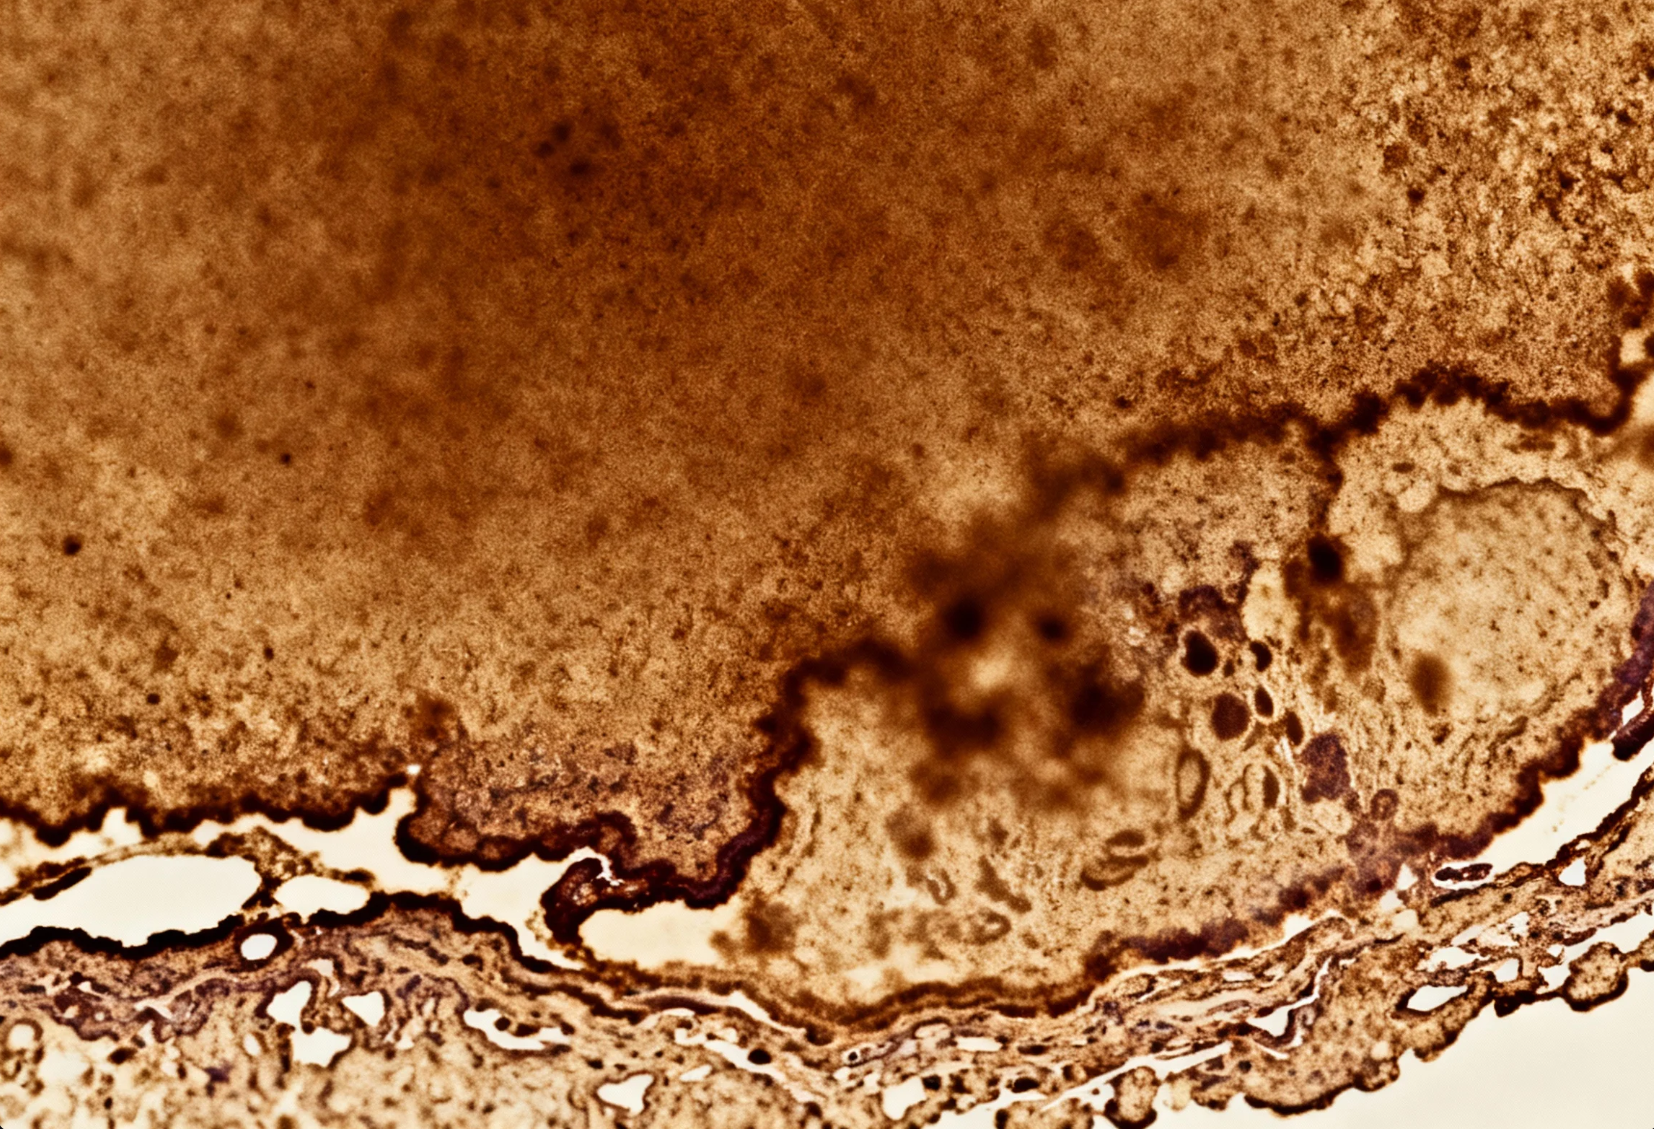

免疫组化(IHC)染色失败可能由抗体、操作流程、样本处理等多环节问题导致。本文以系统性思维为导向,分步骤解析常见问题及解决方案,帮助实验人员快速定位并优化实验条件。

1. DAB显色异常

- 表现:显色过深、弥散或未显色。

- 控制要点:

- 显色时间控制在1~5分钟,显微镜下实时监控。

- 显色后立即流水冲洗,或使用终止液(如2%乙酸)。